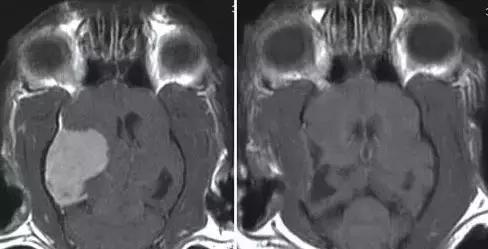

脑瘤是癫痫发作的潜在原因

尤其在老年猫中

左图:一只11岁猫的大脑膜瘤,最近癫痫发作并向左侧盘旋,这种类型的肿瘤往往适合手术切除,大多数猫预后良好

右图:手术切除两个月后的MRI扫描图